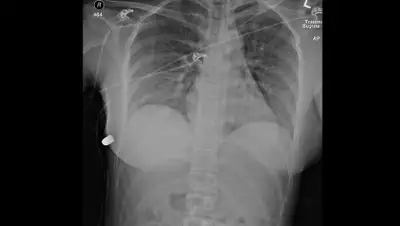

Врачи выяснили, что пуля прошла через левый имплант и он поменял траекторию пули так, что она не попала в сердце. После этого патрон полетел к правому кусочку силикона, да с такой силой, что перевернул его вверх ногами. Затем пуля вошла в грудную ткань и застряла в ней. В имплантах сохранились следы от снаряда.

Пострадавшая отделалась лишь сломанным ребром и лишилась имплантов.